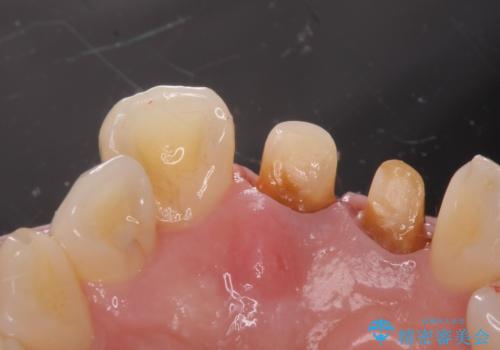

- 前歯の変色を主訴に来院された患者様です。

再根管治療からのやり直しも提案しましたが、特にご希望されなかったためクラウンでの修復処置のみ行います。

歯は根管治療が終了して時間が経つとだんだん茶色く変色していきます。

色調はクラウン修復により改善され、歯並びも術前より改善されたことで大変喜んでいただけました。